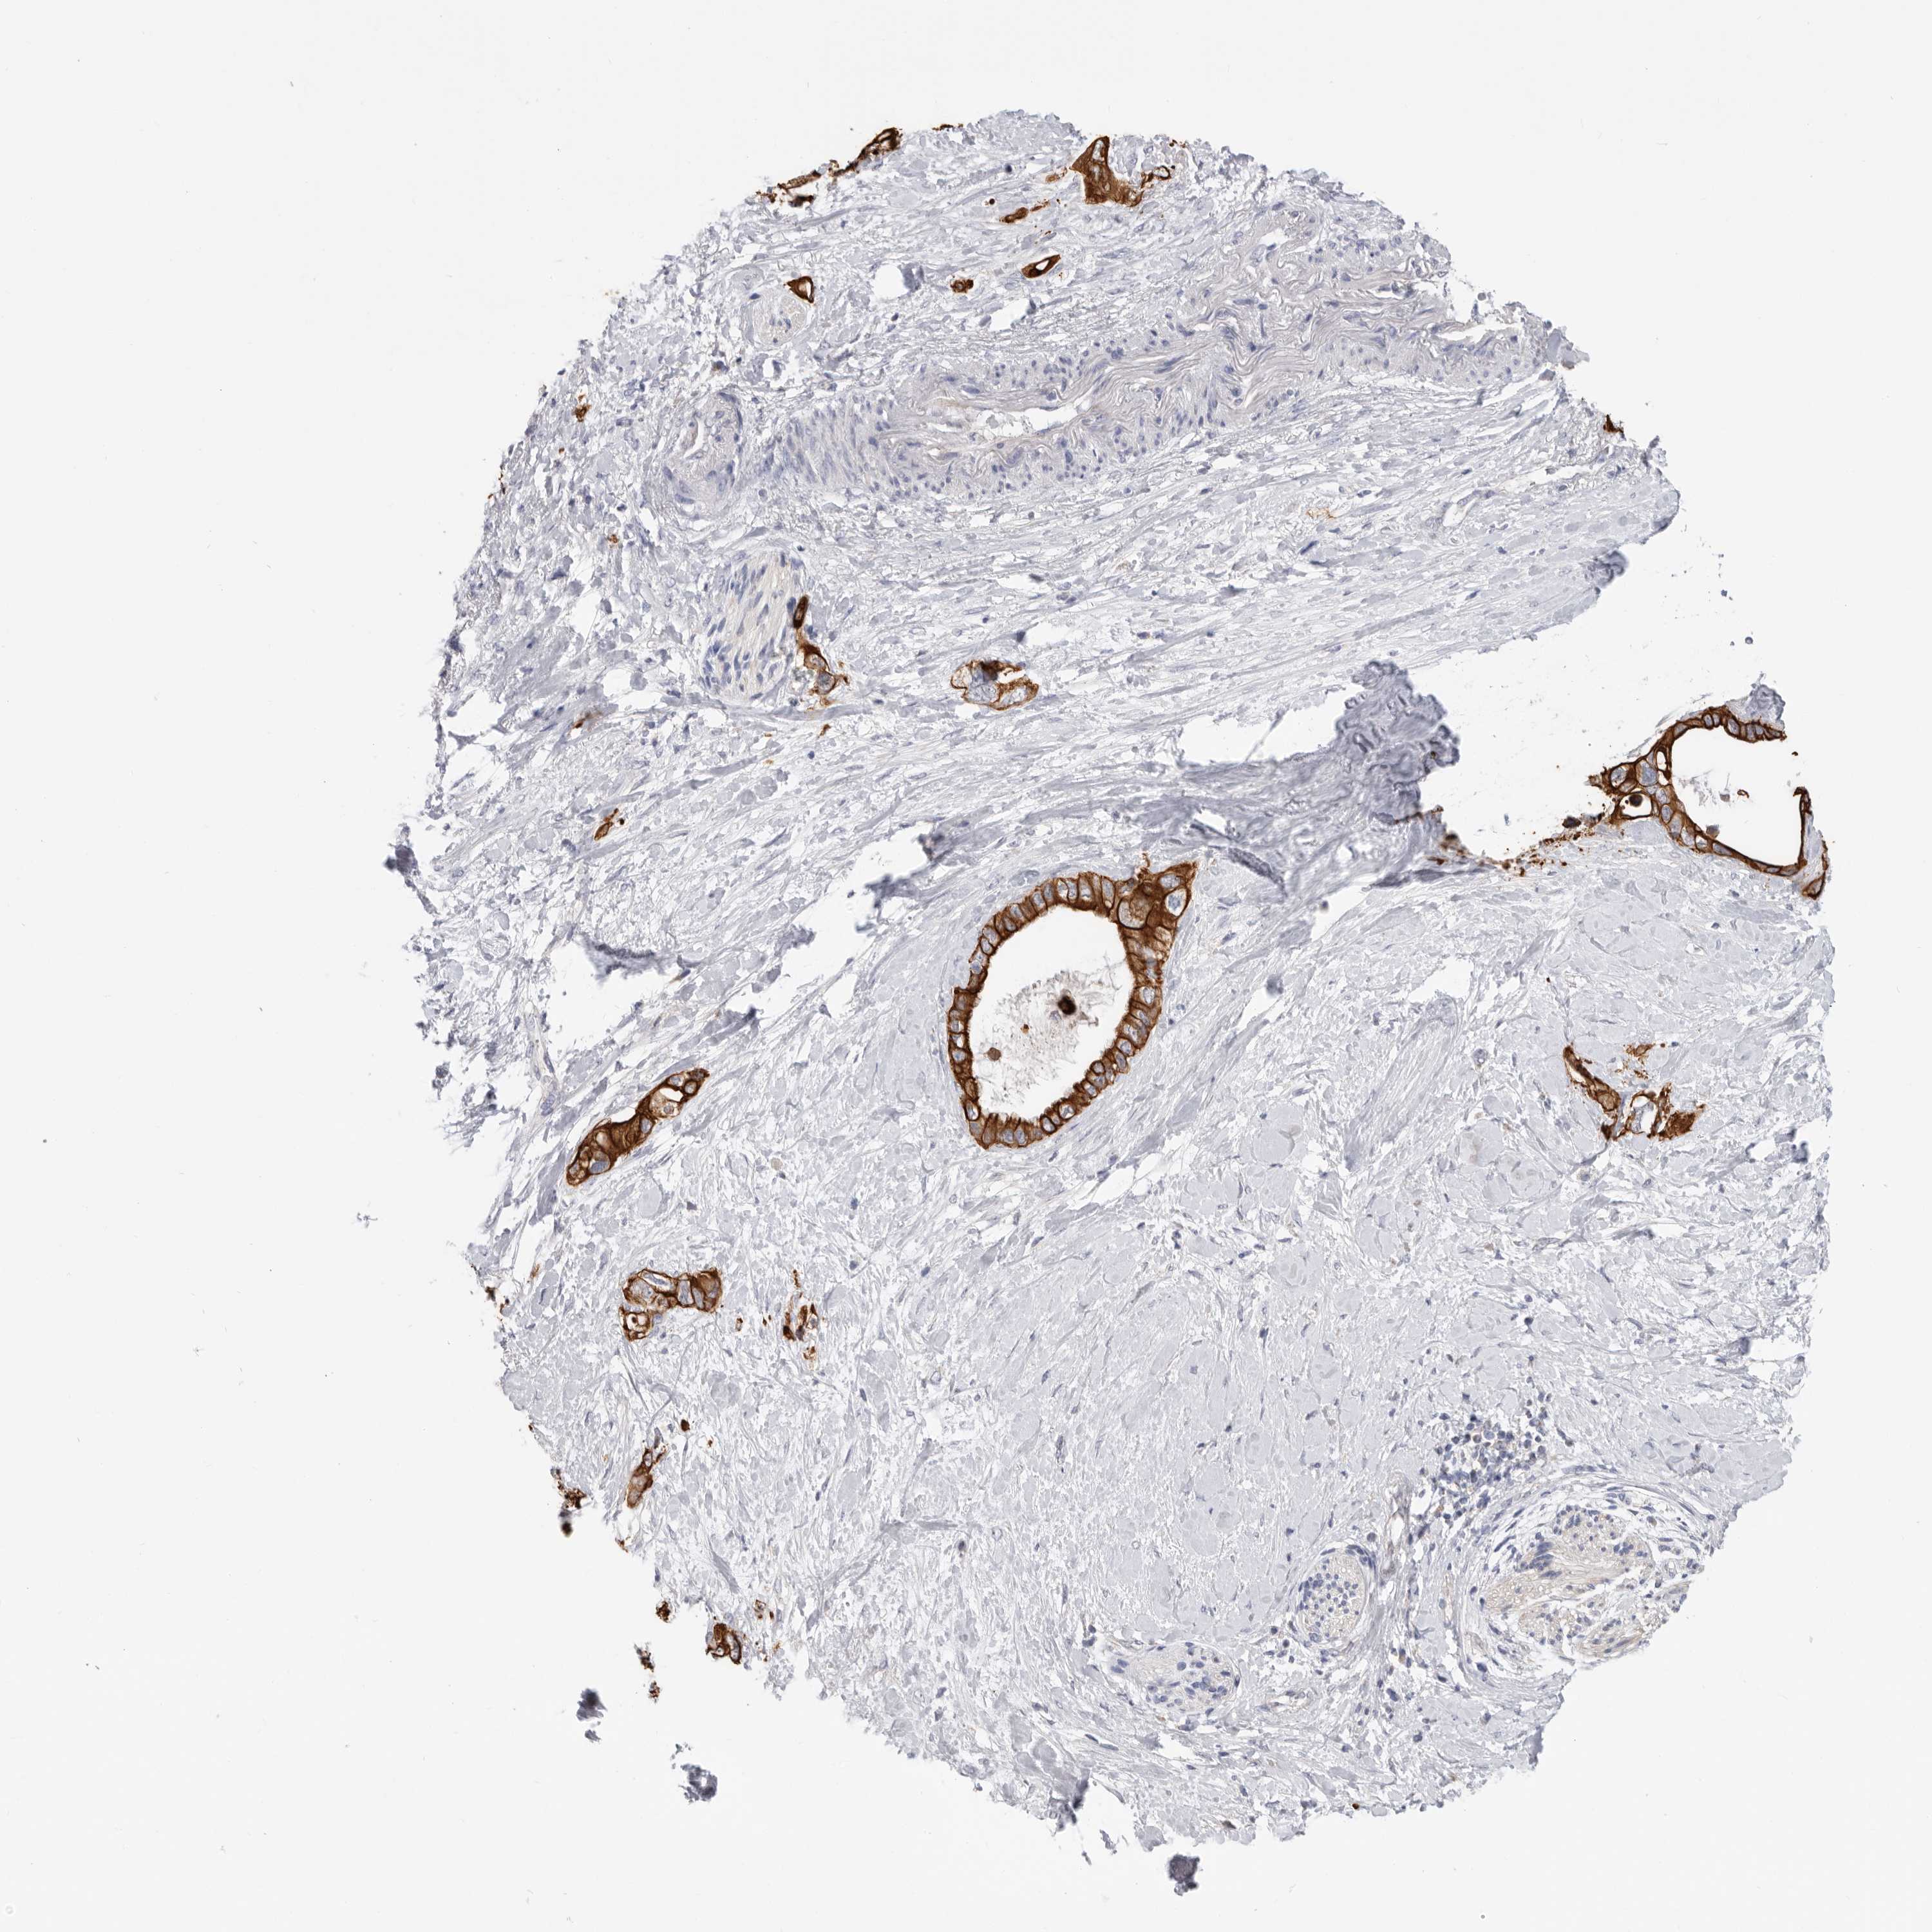

PANCREATIC CANCER - Protein expressioni

A mouse-over function shows sample information and annotation data. Click on an image to view it in a full screen mode. Samples can be filtered based on level of antibody staining by selecting one or several of the following categories: high, medium, low and not detected. The assay and annotation is described here.

Note that samples used for immunohistochemistry by the Human Protein Atlas do not correspond to samples in the TCGA dataset.

Antibody stainingi

Antibody staining in the annotated cell types in the current human tissue is reported as not detected, low, medium, or high, based on conventional immunohistochemistry profiling in selected tissues. This score is based on the combination of the staining intensity and fraction of stained cells.

Each image is clickable and will lead to virtual microscopy that enables deeper exploration of all samples and also displays staining intensity scores, fraction scores and subcellular localization as well as patient and tissue information for each sample.

Antibody HPA027124

Antibody HPA027130

Staining

High

Medium

Low

Not detected

Intensity

Strong

Moderate

Weak

Negative

Quantity

>75%

75%-25%

<25%

None

Location

Nuclear

Cytoplasmic/membranous

Cytoplasmic/membranous,nuclear

Adenocarcinoma, NOS